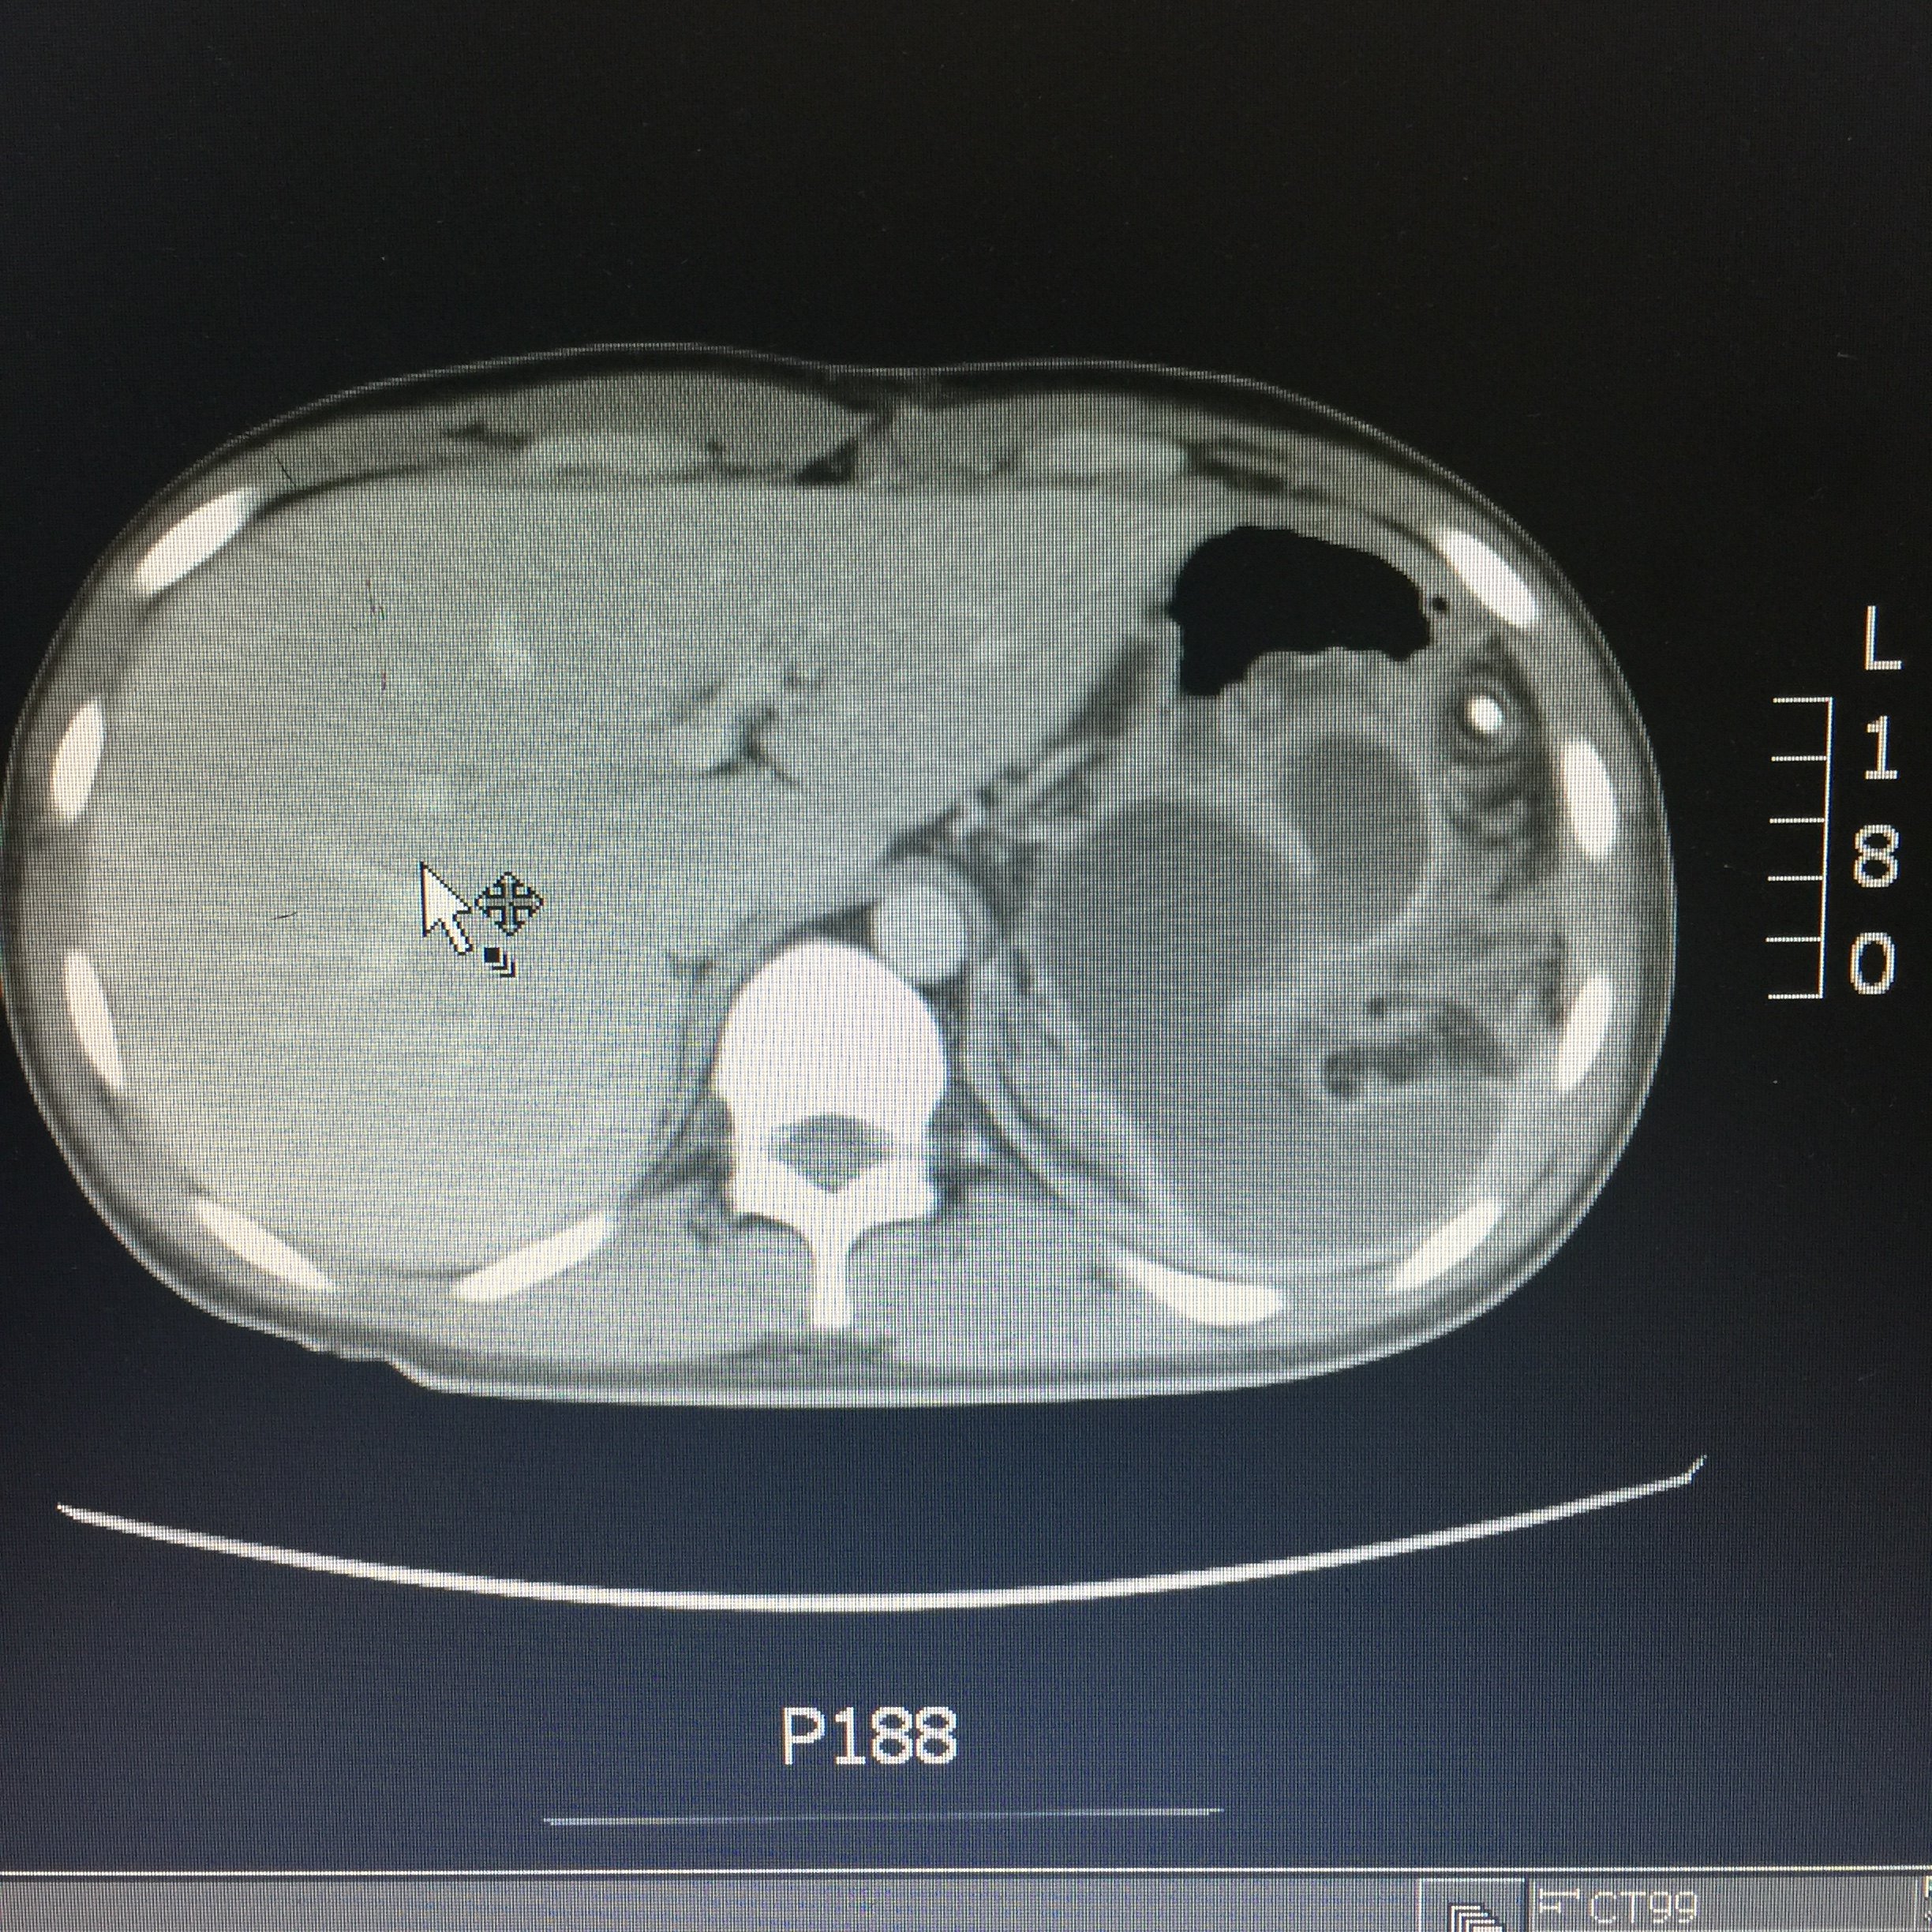

每周诊疗笔记之慢性胰腺炎伴胰头囊肿胰头肿物的外科治疗

图片尺寸3648x2736